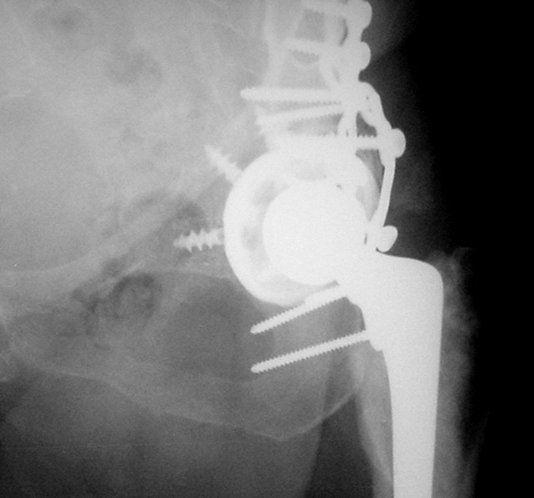

We do not have all information's, like: Judet views, CT, approach used at the time of total hip arthroplasty... what would help, but in general, I would do similar as it is presented with this 75 years old lady:

1. Dislocation of prosthesis

2. Removal of prosthesis head

3. Removal of the cup:we have available some nice, round cutters causing minimal damage of surrounding bone

4. Fix the acetabular fracture (fracture seems to be transverse type!?; it is a real fun to do it with femoral head removed)

5. New metal back cup with multiple holes for screws - improves

osteosynthesis

6. New poly insert and reduction.

7. Femoral fracture - if it is enough space retrograde nail (through the knee), or some plate, fixed angle device.